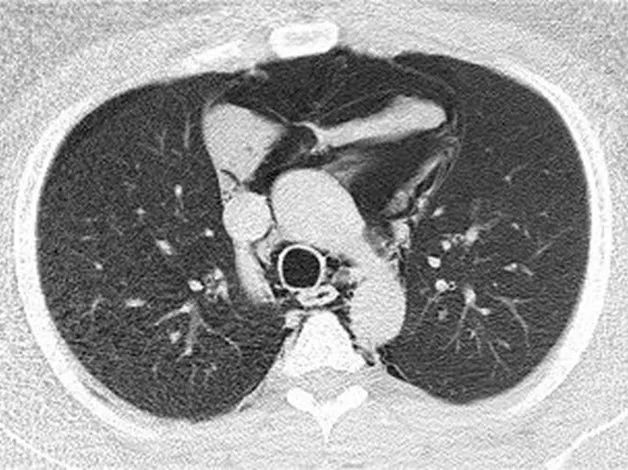

急诊立即请胸外科张能冲医生会诊。张能冲医生诊断小明为剧烈举铁摒气引起的胸腔压力骤增导致的自发性纵隔气肿,推入急诊抢救室对症处理,但小明逐渐出现心率加快(超过130次/分),呼吸急促(频率超过30次/分),氧饱和度需要面罩吸氧及增加吸氧浓度才能维持在95%左右,无法平卧,大汗淋漓,复查胸部CT提示纵隔气肿较前明显进展,双侧气胸。

复查CT较前明显进展